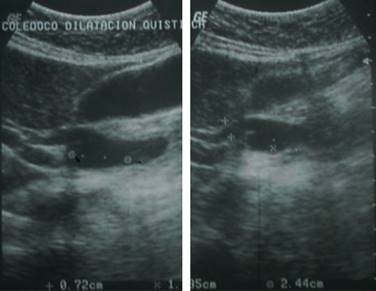

Se le realiza ultrasonido de hígado y vías biliares: hígado normal, colédoco proximal de 7 mm, colédoco distal dilatado de 27 mm con microlitos en su interior, con aspecto en relación con quiste de colédoco, vesícula biliar de 82 x 37 mm pared de 2 mm sin litos, páncreas, riñones y bazo normales.

Impresión diagnóstica (IDX) por ultrasonido: quiste de colédoco con microlitos en su interior (Figura 2).

Figura 2: Se observa USG de hígado y vías biliares, con reporte de quiste de colédoco con microlitos en su interior.

Se realiza otro estudio ultrasonográfico por la consulta externa, encontrándose hígado ecográficamente normal, vesícula biliar anecoica en su interior mide aproximadamente 6.3 x 3.1 cm, pared de 4 mm. Con presencia de quiste de colédoco en región distal con medidas 1.35 x 2.4 x 0.72 cm (Figura 3). Colédoco de calibre normal en su segmento proximal y diámetro de bordes delimitados sin compresión importante de órganos vecinos.

Figura 3: Se realiza otro estudio ultrasonográfico por la consulta externa, encontrándose hígado ecográficamente normal, vesícula biliar anecoica, mide aproximadamente 6.3 x 3.1 cm pared de 4 mm. Con presencia de quiste de colédoco en región distal con medidas 1.35 x 2.4 x 0.72 cm.